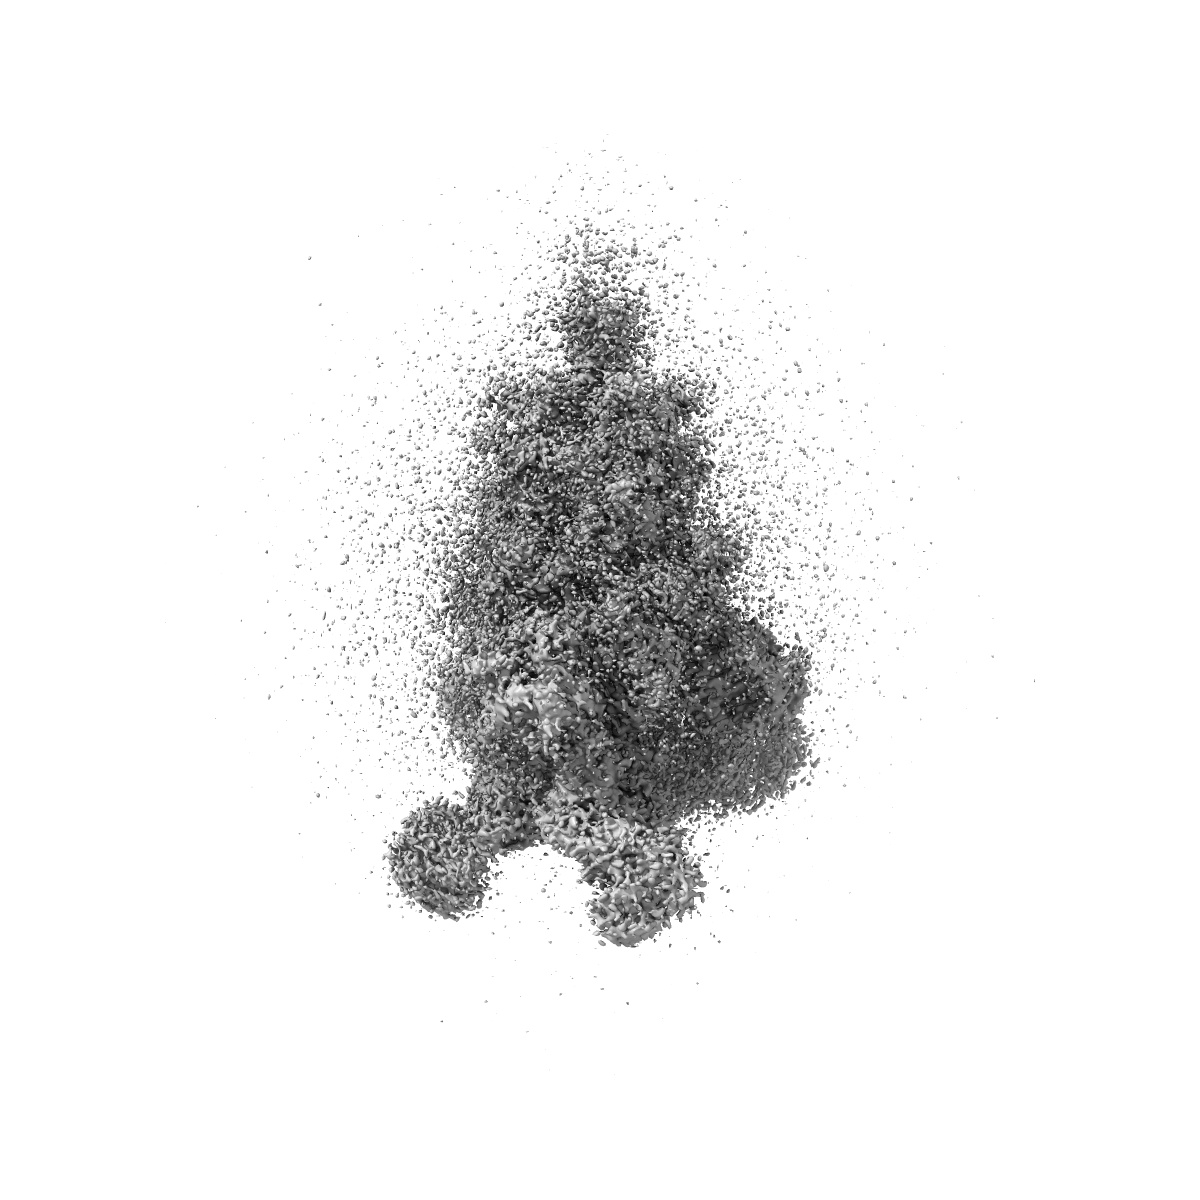

EMD-26678

An antibody from single human VH-rearranging mouse neutralizes all SARS-CoV-2 variants through BA.5 by inhibiting membrane fusion

Single-particle3.1 Å

Sample: One RBD-up state of SARS-CoV-2 D614G spike in complex with the SP1-77 neutralizing antibody Fab fragment